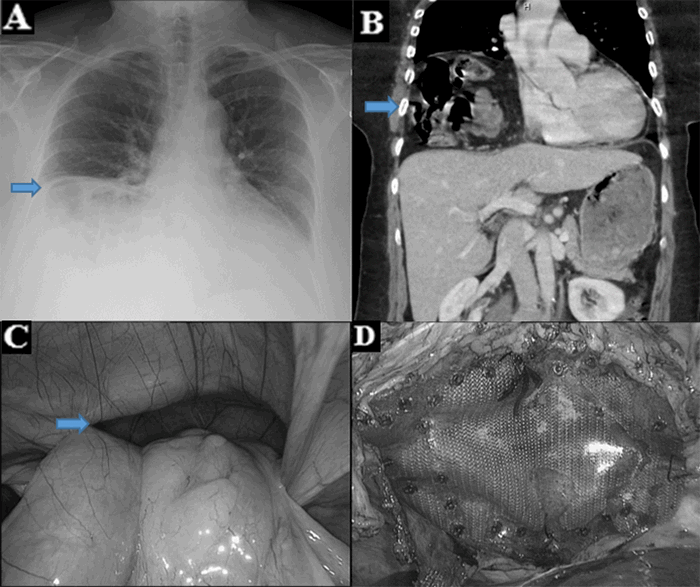

A 67-year-old male with a history of stroke and partial left hemiparesis presented to our facility with right upper quadrant pain. The day before he presented, he had fallen onto his right side while standing; later that same evening, he began experiencing right upper quadrant and lower thoracic pain. He noted some diarrhea but had had no flatus since the night before. The patient was hemodynamically stable with abdominal tenderness in the right upper quadrant with focal guarding. He was febrile and had a leukocytosis. Chest plain film showed what appeared to be air under the right hemidiaphragm (Figure 1a). A CT of the abdomen did not reveal any traumatic injury but did demonstrate a grossly dilated cecum up to 18 cm. It appeared that the cecum had folded superiorly and anteriorly, becoming entrapped between the liver and the diaphragm (Figure 1b). The patient had cecal pneumatosis and an acutely inflamed appendix with a maximum diameter of 16 mm (Figure 1c). He underwent diagnostic laparoscopy, where a dusky and grossly dilated cecum was found to be wedged between the diaphragm and the right lobe of the liver. The inflamed appendix was found to be retrocecal in position. A decision was made to convert to a laparotomy, and we performed a right hemicolectomy with a stapled ileocolic anastomosis. The patient’s postoperative course was uneventful, and he was discharged home on postoperative day six. Pathology confirmed the findings of a grossly dilated cecum and acute appendicitis (Figure 1d).

Figure 1. Cecal bascule with concomitant acute appendicitis. A) Plain film demonstrating dilated cecum under right hemidiaphragm. B) CT Scan of the abdomen showing a dilated cecum between diaphragm and liver. C) CT scan showing cecal bascule with appendicitis. D) Dilated cecum demonstrating the terminal ileum and appendiceal orifice.